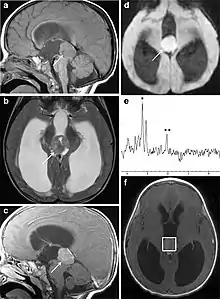

Several imaging methods can be used to diagnose pineoblastoma. Initially, urgent CTs are recommended, followed by MR imaging.[13] CT will show large, multilobulated masses with heterogenous contrast enhancement and peripheral calcification of the pineal gland.[4][3] On MRI, pineoblastomas again appear as masses with heterogenous enhancement. They often appear hypo- to isointense on T1 and slightly hyperintense on T2-weighted images. Some areas of necrosis or hemorrhage may be seen as well. PET-CT has also been used in diagnosis, and shows increased uptake of fludeoxyglucose with pineoblastomas compared to other pineal masses.

Biopsy is required for diagnosis. Pineoblastomas appear as high grade, highly cellular, small blue cells histologically. Features of aggressive malignancies can be seen, like high nucleus-to-cytoplasm ration, poorly differentiated cells, high mitotic activity, and necrosis.[13][3] Homer Wright, or neuroblastic, and Flexner-Wintersteiner, or retinoblastic, rosettes can also be seen. In contrast to other masses of the pineal gland, pineocytomatous rosettes are not present.[13] Immunohistochemistry staining will reveal neuronal, glial, and photoreceptor marker positivity. This includes synaptophysin, neurofilament protein, and CRX, a specific pineal or retinal marker, positive staining.[13][7]